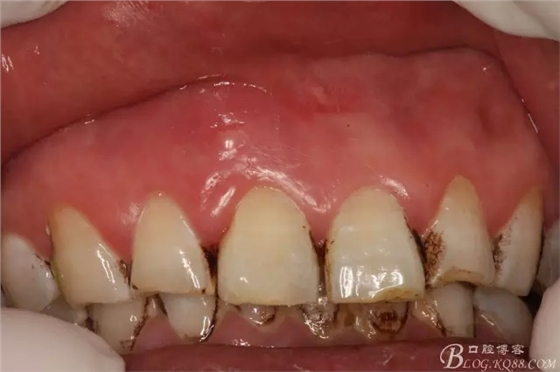

圖2.右上11唇側(cè)根尖區(qū)牙齦紅腫,捫痛明顯、叩診(++)